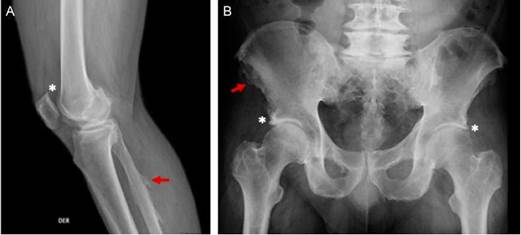

Figura 2 Varón de 65 años, obeso, con cuadro de 15 años de evolución de dolor en columna dorso-lumbar y rodillas asociado a parestesias en miembro inferior derecho. Hallazgos en la radiografía (A) rodilla derecha, excrecencias óseas en patela (*) y en entesis fíbula (flecha roja), (B) osificación en entesis de las espinas ilíacas (flecha roja) y acetábulo (*).